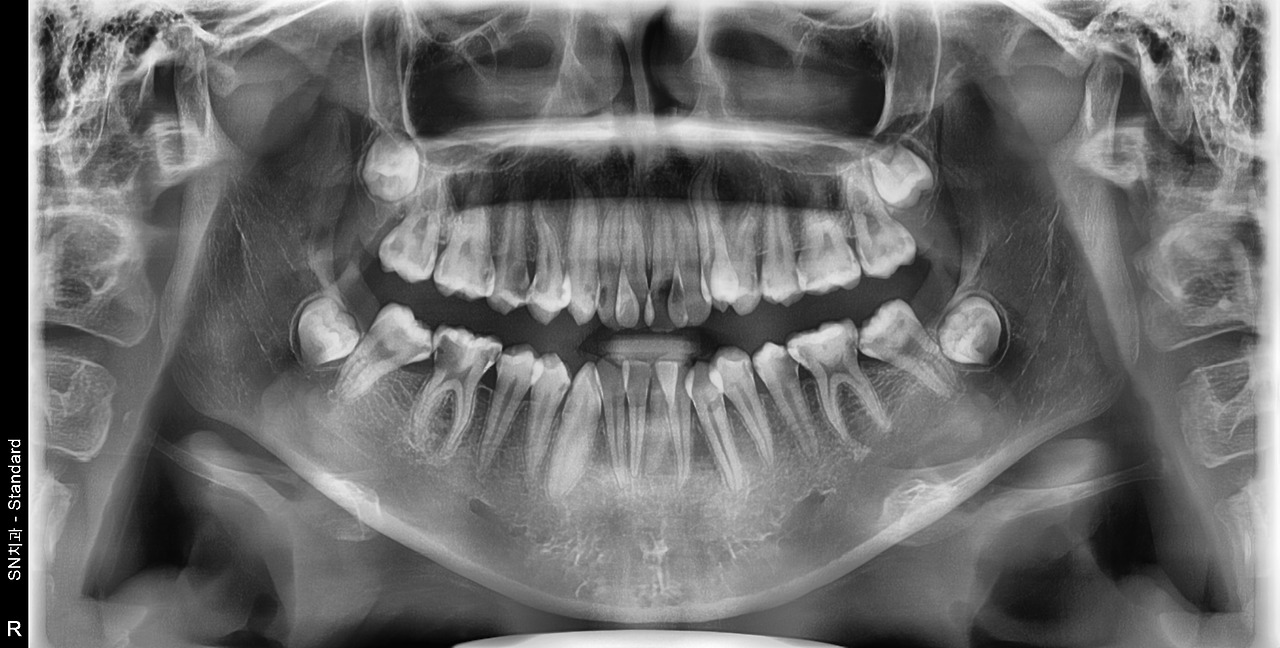

23년 치과의사 생활 중에 top5 안에 들 만큼 치열이 심하게 삐뚤한 아이였어요. 그런데도 1년 전에는 "교정은 하고 싶은데... 치과가 무서워요"라며 계속 망설이더니 결국 치료를 시작하지 않았던 거예요.

1년 전만 해도 간단한 충치치료에다가 교정치료를 바로 시작하면 될 상황이었는데, 지금은 발치해야 할 치아를 결정하고 나머지 24개 치아를 모두 치료한 뒤 교정을 시작해야 하는 상황이 되어버렸습니다.

PX20250823_130415_0000_00013BCB.jpg